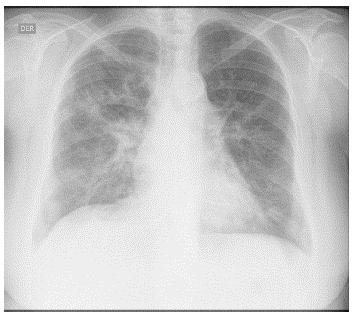

Los hallazgos de laboratorio iniciales revelaron una anemia moderada de volúmenes normales, elevación de la proteína C reactiva (PCR) y un sedimento urinario activo con proteinuria en rango no nefrótico. Los resultados de las ayudas diagnós ticas realizadas se muestran en la tabla 1; la radiografía y la tomografía de tórax se muestran en las figuras 1 y 2, respecti vamente.

Figura 1 Radiografía de tórax. Se observan opacidades alveolo-intersticiales de predominio reticular a nivel parahiliar y basal bilateral.